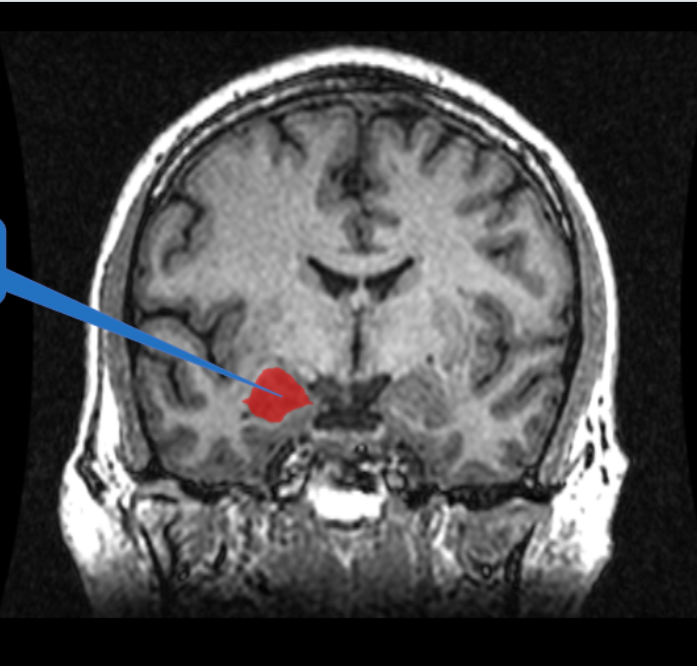

Significance of Henry Molaison

H.M. was having constant grand-mal seizures (epileptic activity). Removal of his bilateral hippocampus reduced his seizures but also gave him memory issues.

What do H.M.’s brain scans show

A loss of volume in the temporal lobe, where the hippocampus is found

Hippocampus Location

Hint from class?

Gray banana = hippocampus

Hippocampal proper

The C-shaped structure of the hippocampus